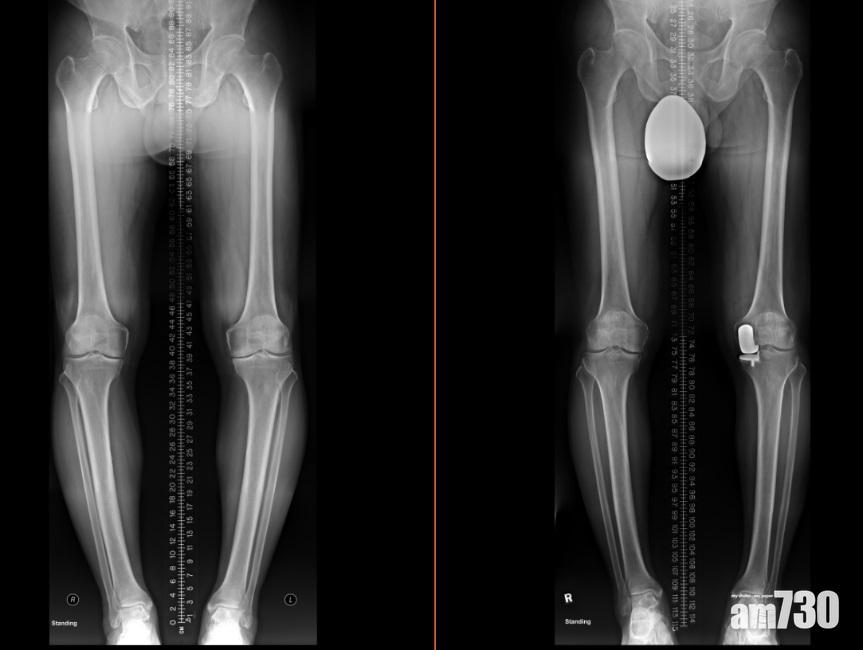

半膝關節置換(右)保留了健康的組織,患者康復後走路的姿勢更自然。(圖片由醫生提供)